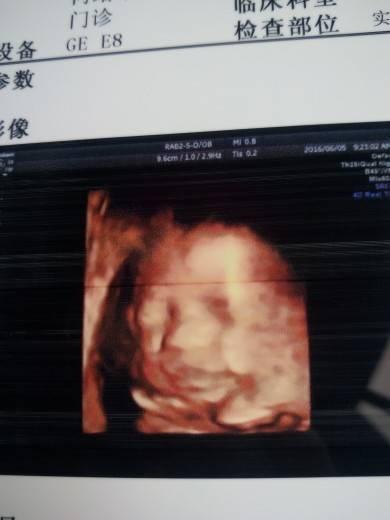

今天去医院做bc了,宝宝依旧遗传着他爸爸的大脑袋,不过好在腿已经不短了。

好欣慰。

一个月没见,长大了好多,虽然看不见模样,但是光看那些数据就觉得很满足。